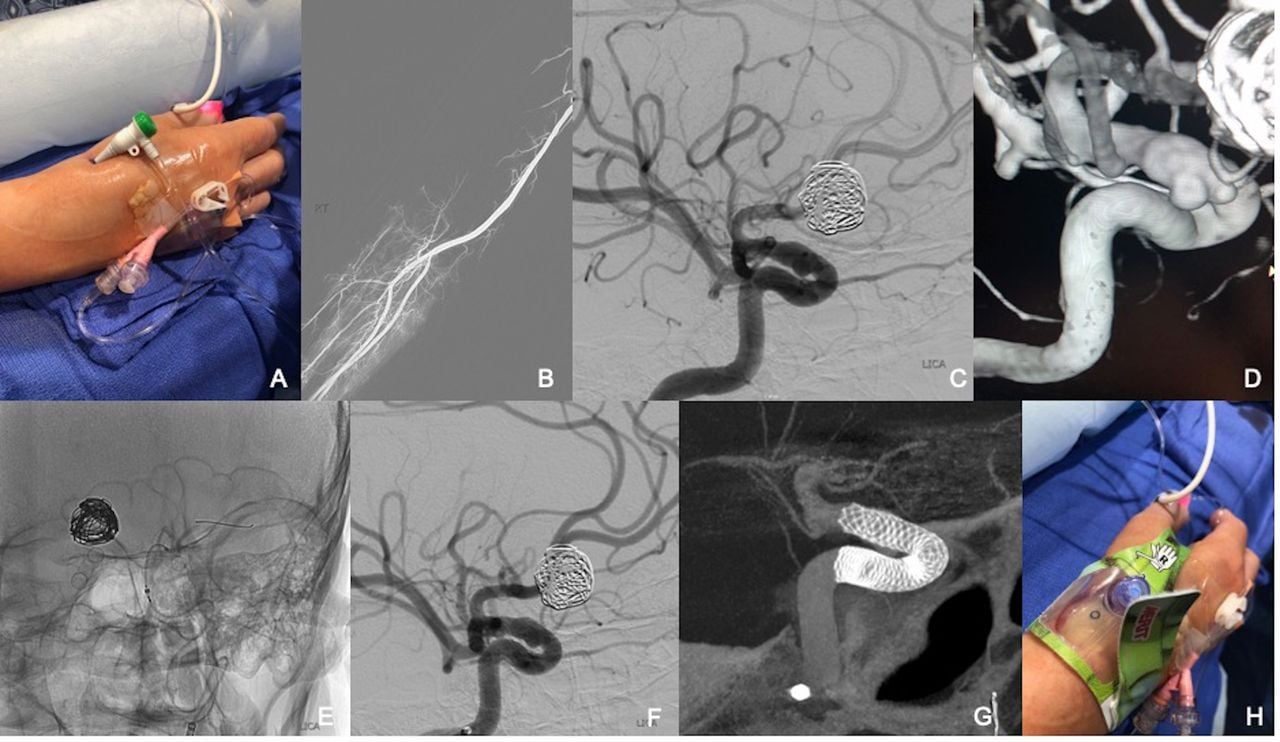

Distal radial access in the anatomical snuffbox for neurointerventions: a feasibility, safety, and proof-of-concept study

Authors: Anna Luisa Kühn, Katyucia de Macedo Rodrigues, Jasmeet Singh, Francesco Massari, Ajit S Puri

Journal of NeuroInterventional Surgery, Published Online First: 08 January 2020. doi: 10.1136/neurintsurg-2019-015604

According to Neurointerventional Radiology Division Chief Ajit Puri, MD "this recent publication which is the first and largest series in the world of patients treated for minimally invasive endovascular Neurointerventional procedures from the artery of the hand (distal radial artery (snuffbox) is now published. This takes a minimally invasive access with a newer novel approach to new heights. Patients love it - a brain aneurysm fixed via the artery of the hand."

Distal radial access in the anatomical snuffbos for neurointerventions